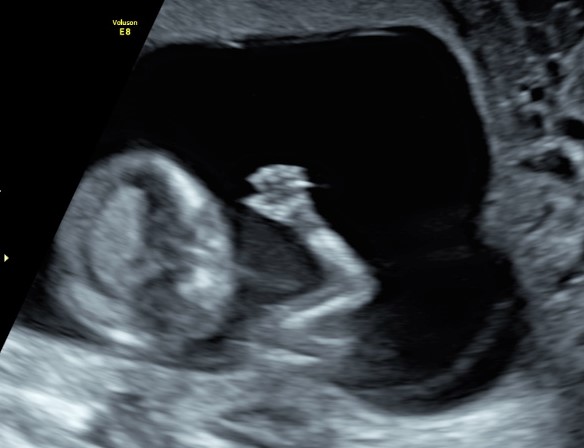

Comincia una fase completamente nuova dove invece di un fagiolino abbiamo a che fare con un piccolo tesoro che salta, saluta e si mostra in tutto il suo splendore a mamma e papà che non possono che rimanere affascinati da come in quei 4/5 centimetri possano concentrarsi così tanto amore e così tanta perfezione.

In questi 4/5 centimetri la risoluzione degli apparecchi moderni riesce a fare una prima valutazione morfologica, per vedere che ci siano tutti i “necessori” ed eventualmente anche accessori: cercando è possibile evidenziare il tubercolo genitale (sempre che il piccolo decida di essere collaborante e mostrare le proprie grazie). Si chiama così perché clitoride e pisellino hanno le stesse dimensioni a questa epoca, ma è possibile riconoscerli in base all’angolo rispetto al corpo: parallelo al corpo per le signorine, verso l’alto per i maschietti. Attenzione però la sensibilità, ovvero quanto ci azzecchiamo, è intorno al 60%.

La parte morfologica è molto importante, riusciamo a studiare l’estremo cefalico – a questa epoca il cervello fetale è molto semplice – , il massiccio facciale con occhi, naso bocca, le orecchie sono abbastanza facili da essere evidenziate. Nel torace oltre ai campi polmonari possiamo vedere il cuore battere ritmicamente e confermare la presenza delle quattro camere cardiache. Nell’addome riusciamo ad evidenziare lo stomaco e l’inserzione del cordone ombelicale. Si nota la presenza della vescica e del tubercolo genitale. Si possono esplorare tutti e quattro gli arti.

Per i genitori vedere sotto i propri occhi prendere forma il tesorino risulta una esperienza indimenticabile e impareggiabile al limite fra incredulità e la sorpresa come tutto sia già presente seppur in scala ridotta.